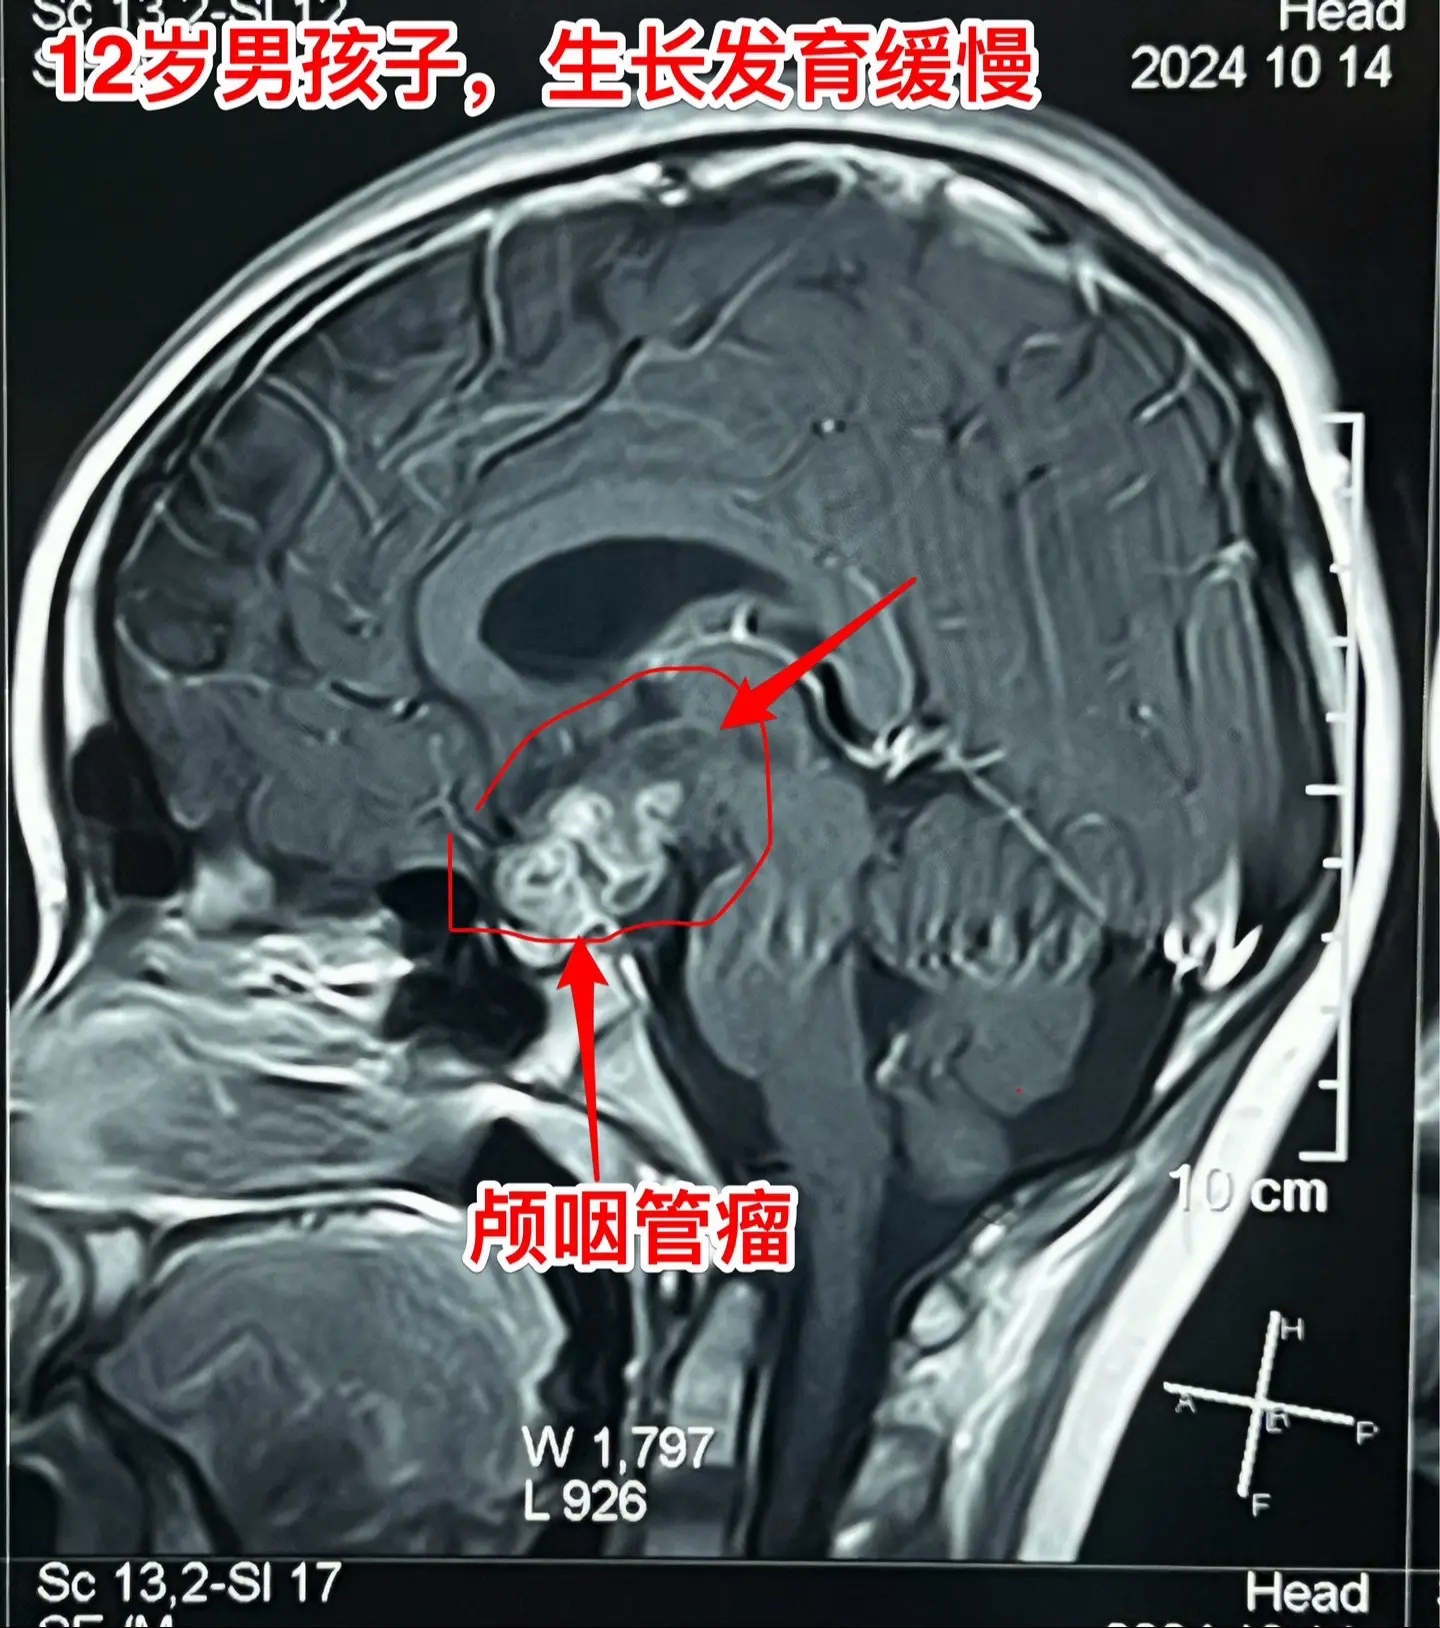

孩子生长发育缓慢,家长要重视。这个12岁的男孩子,在深圳生活,平时爱运...